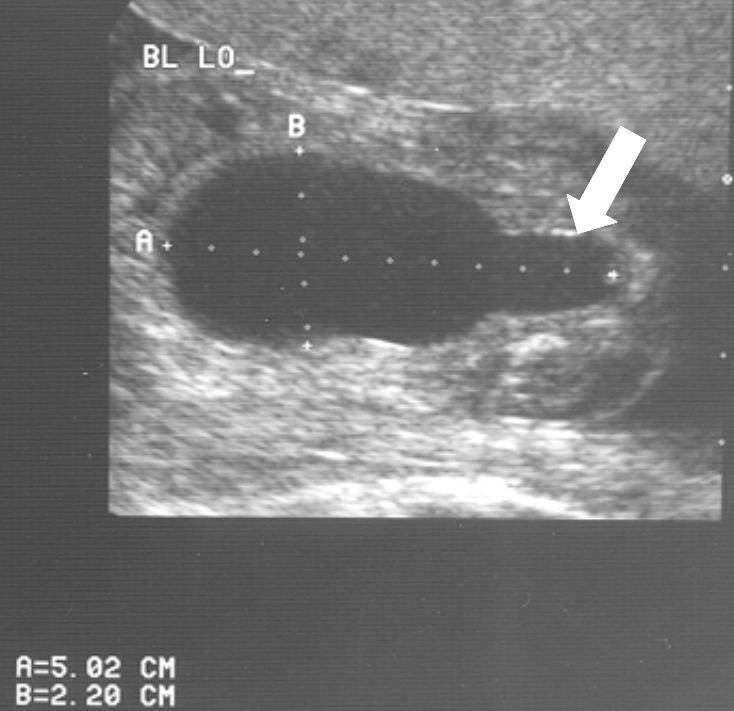

Veel ernstige vormen van urethrakleppen worden al gezien bij echografisch onderzoek vóór de geboorte. Bij de 20 weken echo (of misschien in de toekomst bij een 13 weken echo) worden verwijde nierbekkens en urineleiders gezien. De blaas kan dikwandig zijn, maar ook zeer groot en uitgerekt. Vaak kan het verwijde deel van de plasbuis ónder de blaas worden gezien. Dat noemen we het “sleutelgat teken” omdat de blaas in lengtedoorsnede op de echo er dan uitziet als een sleutelgat. De hoeveelheid vruchtwater kan normaal of verminderd zijn. Als er een verdenking is op urethrakleppen wordt de bevalling gedaan in een centrum waar direct optimale zorg kan worden geleverd aan de pasgeborene.

20 weken echografie: links: dikwandige blaas met verwijding van de plasbuis tot aan de kleppen (pijl): het “sleutelgat teken”. Onder: verwijde urineleiders. Bij kinderen gaan de urineleiders bij verwijding ook erg gekronkeld verlopen.